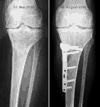

Röntbenbild 11.8.2005 - klicken für grösseer FassungGute Neuigkeiten: Endlich von den Schläuchen und diesem sehr praktischen Infusionsständer befreit! Das erste Mal wieder in seitlicher Lage geschlafen! Welch immensen Geschenke - das erhöht die Lebensqualität schon mal beträchtlich, auch wenn ich noch immer recht schläfrig bin und schwere Augenlider habe. Vorhin schlich ich mich nach dem Röntgen zum ersten Mal an die Sonne raus. Blick auf die Berner Alpen und die Gantrischkette im Morgenlicht... Tut das gut! - Ach ja, Röntgen: Vorerst gibts nur Handyfotos, aber da sieht man schon, dass recht herumgesägt wurde... uff. - Prof. Stäubli war soeben da und ist weiterhin zufrieden. Jetzt gehts bald in die Physio. Das Morgenpanorama ist wieder einmal traumhaft (klicken für grössere Fassung).

15. August, 23 Uhr: Eine Woche danach

Lucia, Ursina und Salome ("in diesem Spital riechts gar nicht nach Spital, eher nach Skilager") versüssten den Abend - und ich sitze im Aufenthaltsraum, sodass mein neuen Zimmernachbar (87 und frisch operiert) in Ruhe schlafen kann. Ist auch ein guter Test für daheim: Wieder möglichst mobil und erfindungsreich, was Transportmöglichkeiten angeht. Ich habe inzwischen bessere Fotos der Röntgenbilder erstellt und ein paar Spielereien gemacht - bitte auf Bilder oder Links klicken für grössere Fassungen:

Auswahl von unbearbeiteten Röntgenbildern in guter Auflösung

Seitliche Bilder, Serie 2001-2005

Vergleich der Tibia vor und nach der Osteotomie, mit Animation - hier ist schön sichtbar, wie die Gelenksachse gemäss dem Plan vom Mai korrigiert wurde

Die aktuellen Röntgenbilder (bitte klicken für grössere Fassungen):

Mal was Neues - Übersicht beide Beine inkl. Becken

Dasselbe Bild wie oben, Ausschnitt Knie

Vergleich 15. August 2005 und 19. September 2005 von vorne

Vergleich 15. August 2005 und 19. September 2005 von der Seite